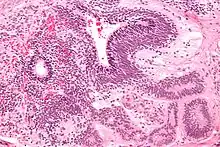

Dysgerminomas are comparable to testicular seminomas and account for approximately 32- 37% of all OGCTs.[1] They are particularly prominent in individuals with dysgenic gonads of 46, XY pure gonadal dysgenesis patients.[1] Based on gross examinations, dysgerminomas are characterized by having a ‘solid, lobulated, tan, flesh-like gross appearance with a smooth surface'.[1] Microscopically, the cellular structure is distinguished by a round-ovoid shape containing ample eosinophilic cytoplasm and an irregularly shaped nuclei.[1] The uniformly positioned cells are separated through the fibrous strands and lymphocytic infiltration is commonly observed.[5]